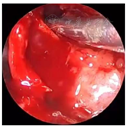

入院后完善术前常规检查,于次日在局麻下行切开引流术,阿替卡因肾上腺素行21-22前庭沟黏膜下局部浸润麻醉,麻醉显效后,自21-22前庭沟处切开黏膜及黏膜下层至囊腔约3 mm水平切口,见大量黄色分泌物溢出,取部分脓液做细菌培养,大量生理盐水冲洗至冲洗,留置橡皮引流条,术后常规予以抗生素控制感染。4 d后检查前庭沟切口处已愈合。经耳鼻咽喉科与口腔颌面外科会诊,决定行鼻内镜下左侧鼻底、下鼻道共同开窗肿物切除术。术中先用彭氏电刀电凝左侧鼻底及下鼻道隆起处黏膜(图5),剥离子自隆起处外侧刺破黏膜进入囊腔,见大量囊液流出,囊液呈浅褐色,略浑浊,吸净囊液后,向后扩大开窗口,保留后部黏膜瓣。剥离部分囊壁送病理检查,清除病变组织后,发现位于囊腔前下壁的不完全的骨间隔隆起(图6)。剥离子在囊肿的左侧上部探查见上颌窦内下骨质缺损,由此刺破软组织进入上颌窦,见有黏液涕流出,扩大上颌窦开窗口,动力系统清除病变组织,使囊肿腔与上颌窦形成一个腔(图7),修剪后部蒂瓣,使之正好贴敷于囊腔后壁(图8),反复生理盐水冲洗术腔,检查无残留,膨胀海绵填塞。手术过程见视频。手术顺利,术后继续行抗生素控制感染,48 h抽出鼻腔膨胀海绵,检查见鼻底及上颌窦开窗口开放良好,腔内有少许血性分泌物,黏膜略水肿。术后病理镜下见被覆鳞状上皮,间质内见急慢性细胞浸润(图9)。术后4 d患者康复出院。